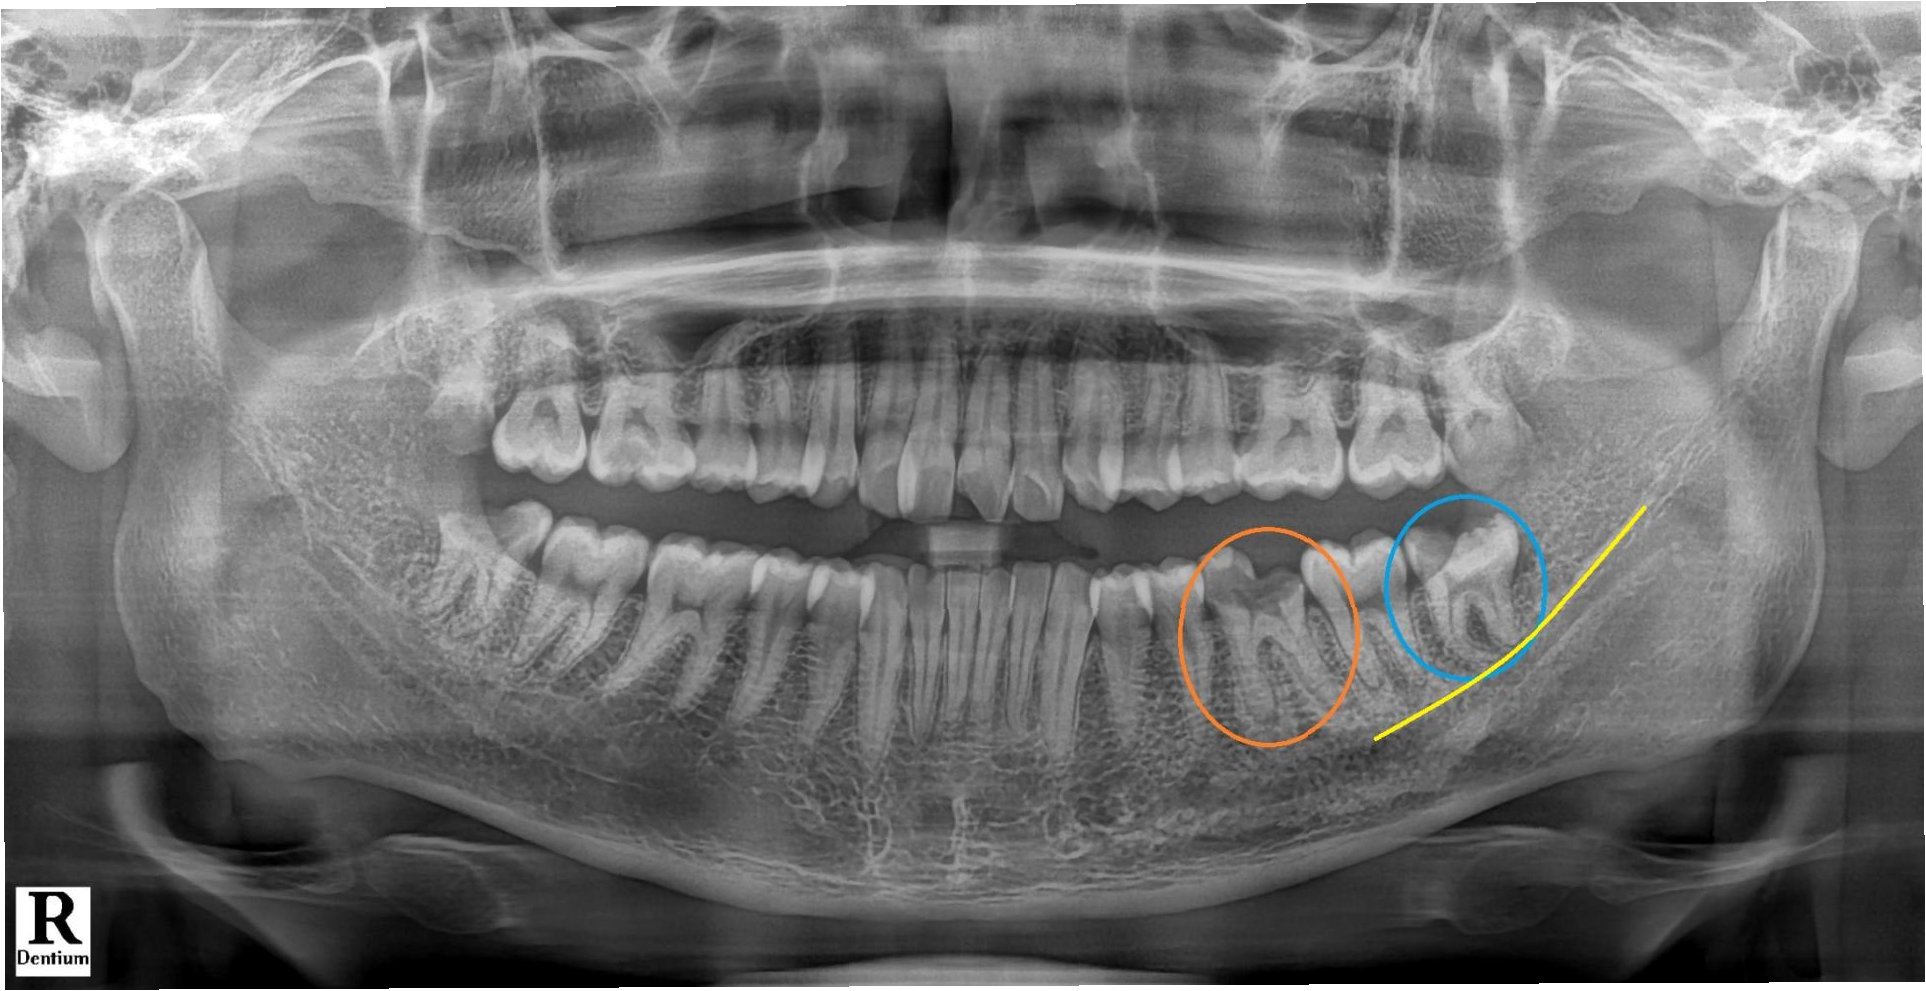

어금니 끝, 잇몸 깊숙한 부위의 통증은 사랑니가 나는 과정에서 생긴 염증일 수 있습니다. 사랑니는 17~25세 무렵 자라며, 턱뼈가 작아진 현대인에겐 비정상적인 위치에 나는 경우가 많습니다. 대부분 가장 안쪽에 위치해 양치가 어려워 충치와 염증에 취약합니다. 일부만 나왔을 때는 잇몸에 염증이 생겨 고름이 나오는 '치관주위염'이 되기도 합니다.

사랑니는 염증이나 충치가 심하지 않으면 보존 치료로 관리할 수 있지만, 염증이 반복되거나 충치가 심하면 발치를 고려해야 합니다. 나이가 들수록 뼈가 단단해져 수술이 어려워지므로, 발치는 보통 20세 전후가 적기입니다. 또한 발치 후에는 감염 등 후유증을 막기 위해 치과의 주의사항을 잘 지켜야 합니다.